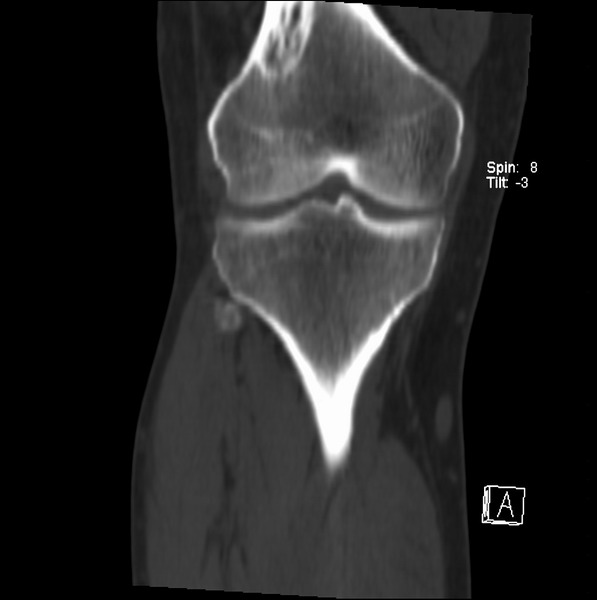

标题: CT21959:骨肿瘤请会诊。

右侧膝关节疼痛一月

男、48

股骨下段、胫骨上段。

1、股骨干骺端病变考虑干骺端纤维性皮质缺损愈后(非骨化性纤维瘤)改变,胫骨近端内生骨瘤(或干骺端纤维性皮质缺损愈后改变);

2、骨关节炎,骨质增生,股骨外侧髁退变性囊肿(关节面软骨下囊肿);

股骨干骺端病变考虑干骺端纤维性皮质缺损愈后(非骨化性纤维瘤)改变,胫骨近端内生骨瘤(或干骺端纤维性皮质缺损愈后改变);

1、股骨干骺端病变考虑干骺端纤维性皮质缺损愈后(非骨化性纤维瘤)改变,胫骨近端内生骨瘤;

股骨干骺端病变考虑非骨化性纤维瘤。

支持非骨化性纤维瘤

非骨化性纤维瘤